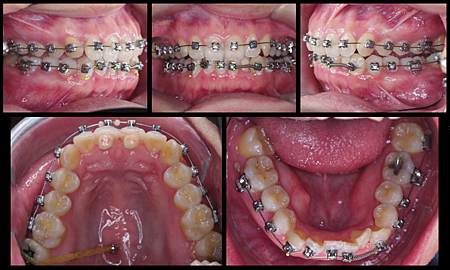

經過兩個禮拜的折磨

舌頭終於比較習慣骨釘和磨人的矯正線

被割出的大裂縫雖然還沒全好,但也好一半啦~

9/25~11/6

戴上矯正器已經經過6個禮拜,

除了前3.4天,牙齒痠軟到我完全不想吃東西外

戴牙套這件事對進食幾乎沒帶來困擾~(不考慮進食後的清潔...)